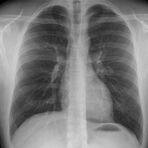

Konventionelles Röntgen

Der Begriff Röntgen, oder auch Röntgendiagnostik bezeichnet ein Verfahren in der Radiologie, bei dem von einer Röntgenröhre elektromagnetische Wellen (Röntgenstrahlen) durch die zu untersuchende Körperregion des Patienten gesendet werden. Je nach Dichte der Gewebeart des Körpers (z.B. Knochen oder Lunge) werden die Röntgenstrahlen im Körper unterschiedlich stark abgeschwächt. Ein digitaler Detektor empfängt dann die Röntgenstrahlen, die in abgeschwächter Form den Körper wieder verlassen haben. Daraus wird das Röntgenbild erzeugt.

Die Röntgenuntersuchung ist weiterhin eine unverzichtbare Basisdiagnostik. Viele Fragen können in der medizinischen Diagnostik mit einer konventionellen Röntgenaufnahme geklärt werden.

Durch den Einsatz neuester volldigitaler Röntgentechnik wird die Strahlendosis auf niedrigstem Niveau gehalten.